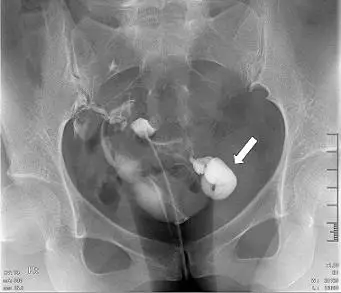

34歲女性子宮輸卵管攝影檢查呈現如圖,箭號所指之病灶,下列何者為最恰當之診斷? 圖片描述

從所示的 HSG 正位 X 光片可見子宮腔注入對比劑後,對比劑沿雙側輸卵管向周邊流出。在右側(箭號處),對比劑在近端管口之下累積成一大腔狀結構,管壁細薄、形狀呈梨狀或「香煙袋(tobacco pouch)」樣,並無明顯的腹腔逸散,顯示遠端輸卵管阻塞後內部積液。此腔狀擴張與對比劑無法通過證實管腔封閉。

典型 HSG 表現為遠端管口阻塞、管腔細長而擴張,末端梨狀或沙漏狀,對比劑囊狀聚集,無腹腔逸出,並常見「waist sign」(兩側管壁向內凹陷)或「tobacco pouch」外觀。此與題中影像相符(pubmed.ncbi.nlm.nih.gov, link.springer.com)。

箭號處所示為典型的 hydrosalpinx,在遠端阻塞後出現管腔擴張、梨狀/沙漏狀囊性積液且無對比劑逸出,符合輸卵管積水特徵,故以 A 最恰當。